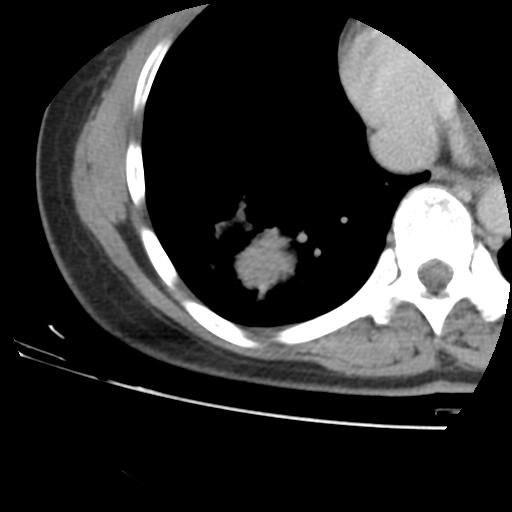

右肺下叶类癌

女 46岁,咳嗽咳血10月

【linyiming】右肺下叶见类圆形软组织影,边缘欠规整,略分叶状。考虑炎症假瘤可能?

未排除周围型肺癌。建议CT增强。

【刚起步】只有想不到的,没有长不到的。实性结节,强化明显,病人咳血,肺癌不能除外。

【aosangwa】肺癌的主要特征是:毛刺征、分叶征及胸膜凹陷征,此病例位于右肺下叶距胸膜很近,但没有胸膜凹陷征,其周围像示渗出性病变,病灶在两窗上没有大小没有发生大小改变。

考虑其良性肿瘤,炎性假瘤可能性大,其主要鉴别是:结核球、周围型肺癌、血管瘤

病理诊断类癌(周围型)。